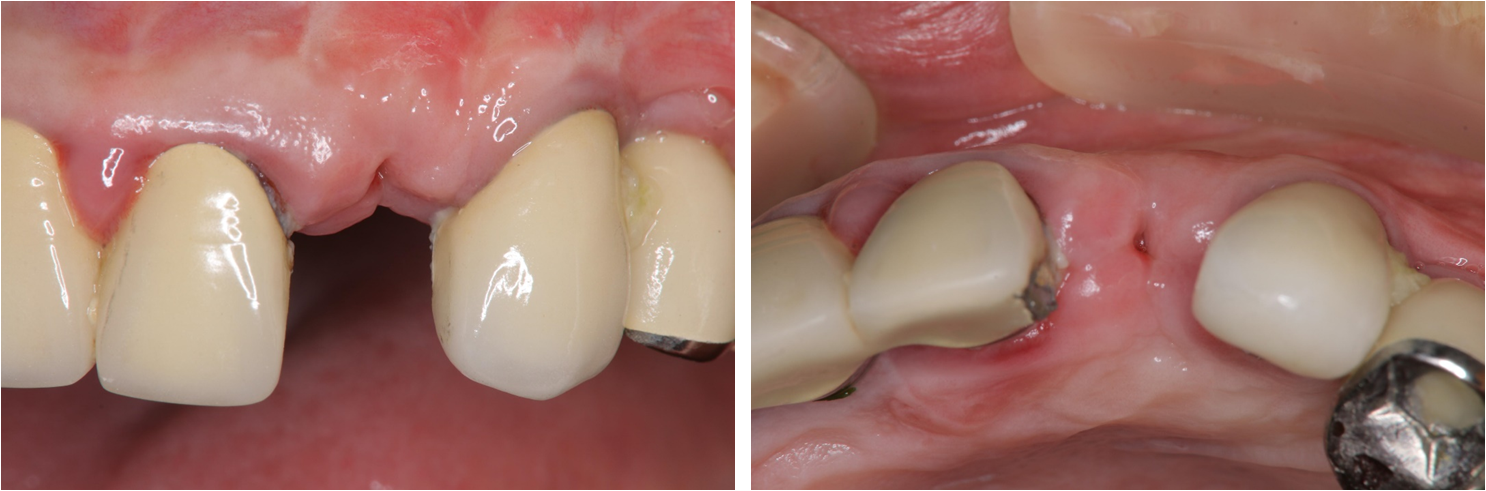

治療前,左上側門齒牙齒斷裂

側門齒之前有做根尖切除,支撐性不足